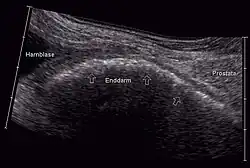

Sonographisch werden insbesondere Restharn- und Prostatavolumen beurteilt. Die Sonographie ermöglicht auch die Erkennung eines (meist urodynamisch besonders relevanten) vergrößerten Mittellappens. Die Ultraschalluntersuchung wird meist transrektal ausgeführt, ermöglicht aber auch transabdominal eine gute Bestimmung des Restharnvolumens und bei voller Blase auch von Prostatavolumen, endovesikalem Mittellappen und der Anhebung der Blase durch das BPH (intravesikale prostatische Protrusion).[21] Die erhobenen Befunde werden zur Beurteilung des Progressionsrisikos und der Notwendigkeit einer Behandlung verwendet. Eine pathologisch erhöhte Restharnmenge alleine ist nicht beweisend für eine den Harnfluss behindernde BPH. Mittels Sonographie des oberen Harntraktes kann eine relevante Harnstauung ausgeschlossen werden. Sogenannte bildgebende Verfahren wie Computertomografie (CT), Magnetresonanztomografie (MRT) oder Ausscheidungsurografie sind zur Diagnose einer BPH nicht angezeigt.[22] Die Durchführung eines Urogramms ist bei Verdacht auf eine Erkrankung der Nieren angezeigt.